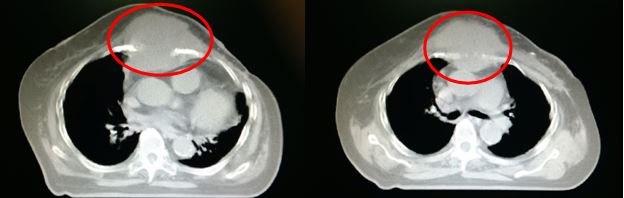

Hình 1. Hình ảnh CT ngực: khối u vú trái tiến triển xâm lấn thành ngực, kích thước 6x7 cm (Vòng tròn đỏ)